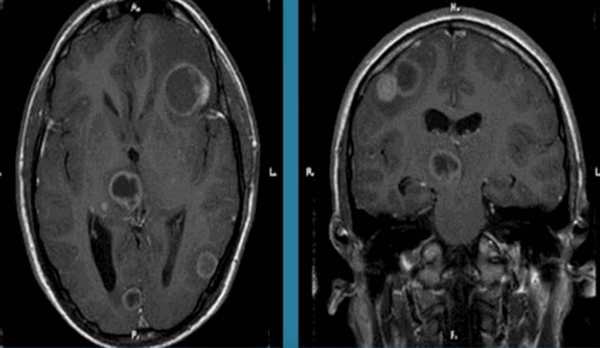

Результаты МРТ мозга с контрастом показывают наличие опухоли (пораженная часть выделена красным): патологический очаг, в отличие от здоровой ткани, интенсивно накапливает усилитель, четкие границы и связь с твердой оболочкой дают возможность предположить доброкачественное образование